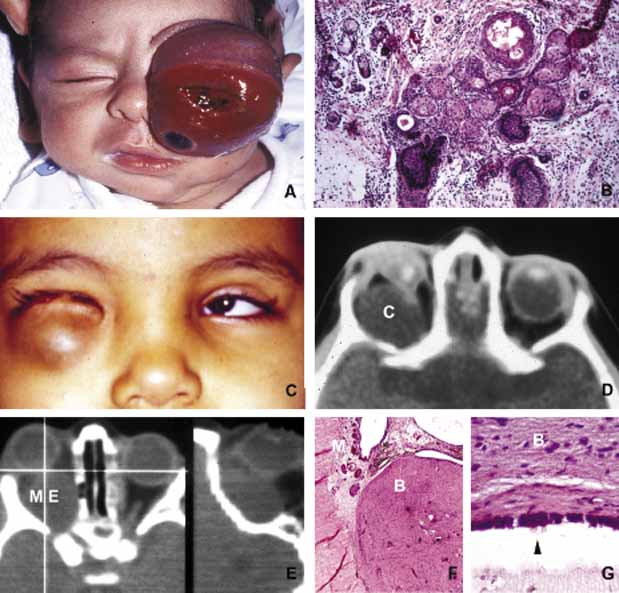

In cases of microphthalmos and anophthalmos the orbit may be well formed but does not develop to a full adult volume. The mechanism by which the presence of the globe effects the growth of the orbit is not well understood. Microphthalmos may be associated with a colobomatous cyst as a result of the abnormal closure of the embryonic optic fissure leading to the prolapse of neuroectodermal tissues into the orbit (Fig. 1) This cystic structure may increase rapidly in size to overshadow the abnormal globe and may be confused with a neoplasm. When cystic lesions in the orbit are suspected imaging studies should be performed not only to look for other intracranial abnormalities but also to establish the possible connection of the cyst to the colobomatous globe versus to abnormally formed meninges.11 Macrophthalmos (buphthalmos) may also rarely develop as a congenital anomaly in patients with Sturge-Weber syndrome and rarely in neurofibromatosis type I.

Fig. 1 Congenital lesions. A very large cystic teratoma of a 1-month old child (A). B. Histology of this lesion that contains a variety of tissues, endodermal, ectodermal, and mesenchymal. An orbital cyst (C) in an orbit containing micro-ophthalmic globe. C, D. The protrusion of the cyst inferiorly creates a mechanical lower lid ptosis that narrows the right maldeveloped conjunctival sac even further. Axial and sagittal CT scan showing a meningoencephalocele (ME) occupying the entire orbit (E). The histopathologic examination of the lesion revealed both meningeal (M) and brain (B) tissues (F). The high-power histopathology reveals ciliated ependymal cells lining some of the cystic spaces (arrowhead) (G).

Cephalocele results from the extension of maldeveloped CNS tissues including meninges (meningocele), brain parenchyma (encephalocele), and the combination of the two (meningoencephalocele) into the orbital cavity.12,13 Intraorbital cephaloceles may develop anteriorly at the suture lines of orbital bones or posteriorly extending into the orbit from orbital fissures and the optic canal. Depending on the combination of these herniations they contain brain and/or meningeal tissues (Fig. 1). Aberrant fibroglial tissue has also been described in the orbit.14

Teratoma is a germ-cell tumor that contains tissues derived from endoderm, ectoderm, and mesoderm22 (Fig. 1). Therefore, these lesions may contain skin, bowel, lung, brain, thyroid, cartilage, and bone tissues. Most teratomas develop unilaterally and in girls. A majority of these congenital tumors are benign. Occasional reports have documented malignant transformation within orbitocranial teratomas.23 However, these benign tumors continue to grow after birth because of the collection of secretions from different tissues into the partially cystic spaces of the tumor. Some teratomas create massive proptosis and most can only be treated by exenteration. However, some of these lesions have recently been reported to be removed surgically with preservation of the globe and other vital orbital structures.